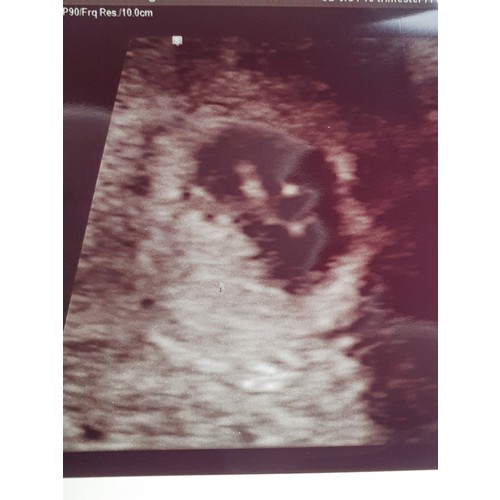

Dit was mijn echo met 6+5